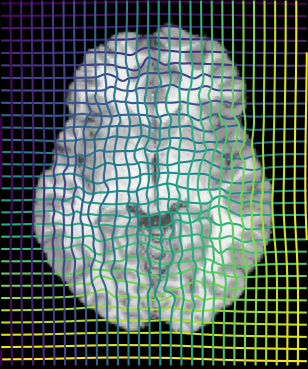

Inverse consistent rigid, affine, nonparametric, and MLP registration. We train networks on MNIST 5s using the methods in Secs. 3 and 4, demonstrating that the resulting networks are inverse-consistent. Our TwoStepConsistent (TSC) operator can be used on any combination of the networks defined in Sec. 3. For demonstrations, we join an MLP registration network to a vector field registration network, and join two affine networks to two vector field networks. Fig. 2 shows successful inverse-consistent sample registrations.

| Moving Image | Warped Image | Fixed Image | Moving Image | Warped Image | Fixed Image |